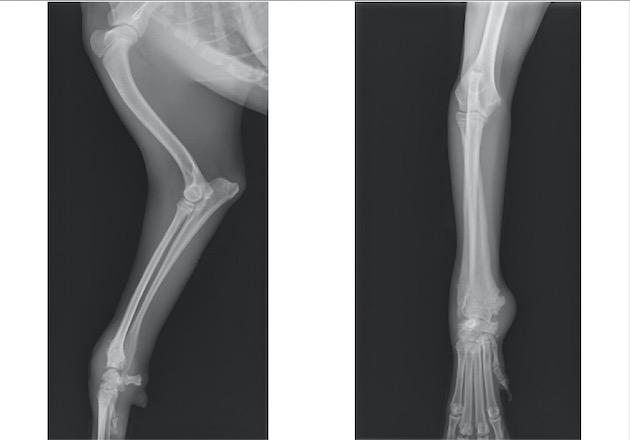

ソファーの背もたれから落下後、右前肢居城を主訴に来院。

両前肢の明らかな左右差は認められませんでしたが、触診検査において右側肘関節における圧痛を確認しました。

単純X線検査を実施したところ、上腕骨遠位外顆骨折が認められ、上腕骨遠位の成長板をまたぐ骨折であったことから成長板骨折(Salter-Haris Type4)と診断して外科的処置を実施しました。

背掌像より上腕骨遠位外顆の骨折が認められました

内外側の上腕骨顆を皮質骨スクリューとキルシュナーワイヤー、外側上顆をキルシュナーワイヤーにて固定しました